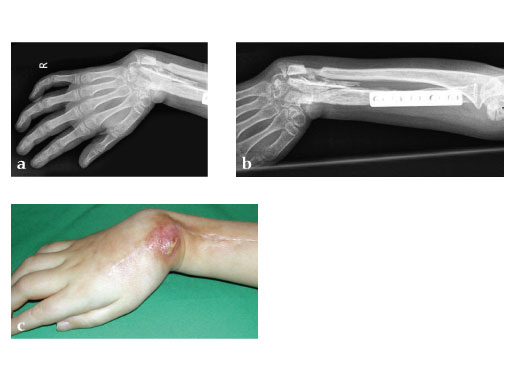

Fig 3a: Microvascular osteocutaneous free fibula flap for reconstruction of radius and dorsal skin.

Fig 3b: Proximal osteosynthesis with two screws and arthrodesis of wrist wrist with LCP 2.7.

Fig 4ac: Postoperative.